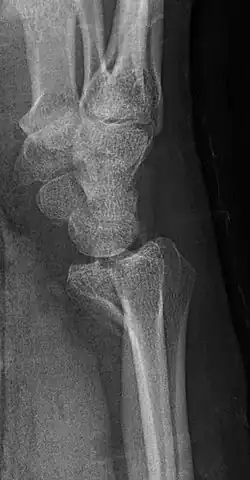

A Barton's fracture is a type of wrist injury where there is a broken bone associated with a dislocated bone in the wrist, typically occurring after falling on top of a bent wrist.[1] It is an intra-articular fracture of the distal radius with dislocation of the radiocarpal joint.[2]

There exist two types of Barton's fracture – dorsal[3] and palmar, the latter being more common. The Barton's fracture is caused by a fall on an extended and pronated wrist increasing carpal compression force on the dorsal rim. Intra-articular component distinguishes this fracture from a Smith's or a Colles' fracture. Treatment of this fracture is usually done by open reduction and internal fixation with a plate and screws, but occasionally the fracture can be treated conservatively.[4]